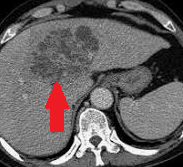

Presence of multiple metastases in the right lobe of the liver, 3 years after left hemicolectomy (Courtesy Dr. V. Penopoulos)